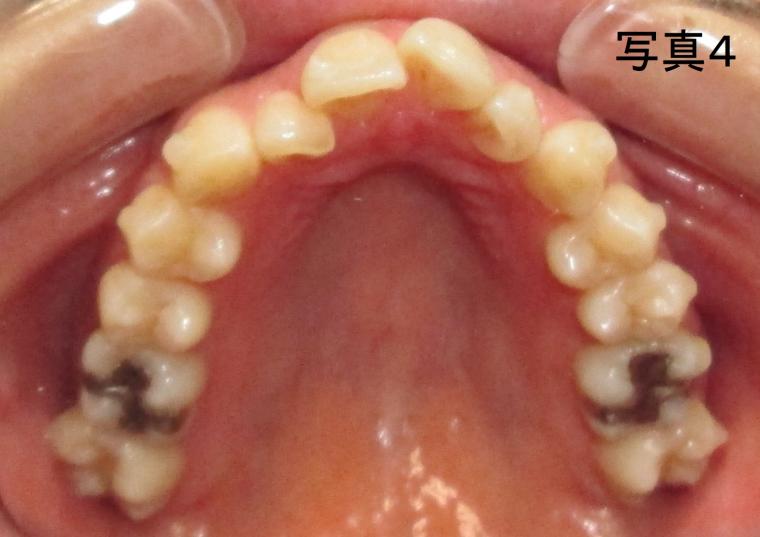

アライナーは5ステージ目に入った本日は口腔内の写真撮影を行いました。(写真1~5)

歯磨きの時など毎日歯並びを見ているので、歯が動いている実感はありませんでしたが、アライナー装着前の写真と比較すると上の前歯の重なりが軽減されていること、まだデコボコはありますが舌側に倒れている下の前歯が唇側に動いていたのが分かって感激しました